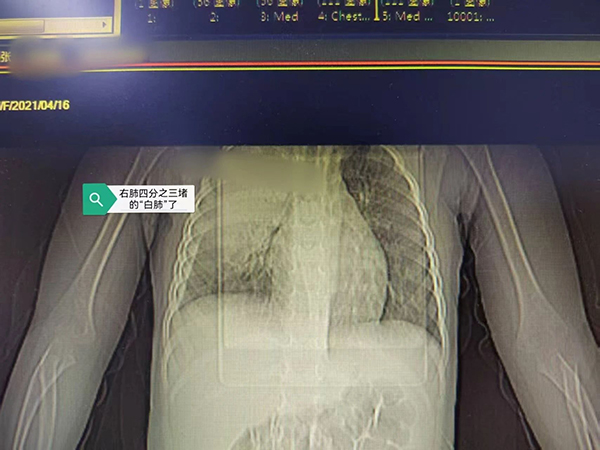

【健康科普】被“啃”的肺子...

近日,我院小儿呼吸科收治了一名4岁小患者,他因持续高热、咳嗽10天入院。入院前虽经很多治疗,但病情仍逐渐加重,来诊时血常规显示白细胞高达2万(20×10⁹/L),炎症指标CRP 高达235...